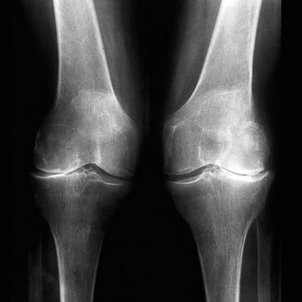

L'Organització Mundial de la Salut prediu que per a 2020 més de 579 milions de persones al món patiran artrosi, una malaltia degenerativa que consisteix en un desgast del cartílag articular. Dins dels diferents tipus que es poden patir, es troba el de genoll, que és bastant comú.

Un altre símptoma és el bloqueig. Amb el pas del temps, els músculs del genoll poden debilitar-se i tota l'estructura articular pot tornar-se inestable. La debilitat general del genoll pot fer que aquesta cedeixi o es doblegui. La unió també pot enganxar-se o bloquejar i no es pot doblegar o redreçar bé. També és típic sentir sons de cruixits o esclats, o un grinyolar als genolls en moure's. Aquests símptomes solen passar quan s'ha perdut part del cartílag llis que permet el rang del moviment suau. L'artrosi torna les superfícies rugoses i els esperons ossis es freguen entre si mentre es mouen les articulacions.